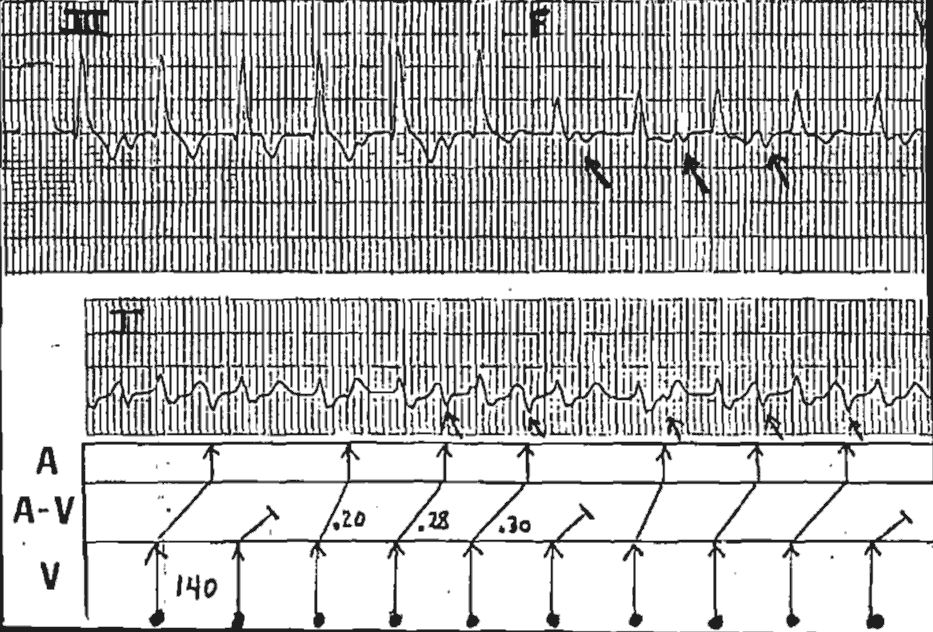

There are P waves intermittently present – the negative deflections in Leads II,III and AVF (arrows on image).

The ladder diagram provides the official solution. There is a Tachycardia at 140/min with retrograde (V-A) conduction.

Note the changing R-P intervals, consistent with Wenckebach prolongation, unit a “dropped P waves” occurs.

Conclusion: the rhythm is Ventricular Tachycardia with 4:3 Wenckebach V-A Conduction.

The Ventriculo-Atrial association proves that the ventricle is in command.